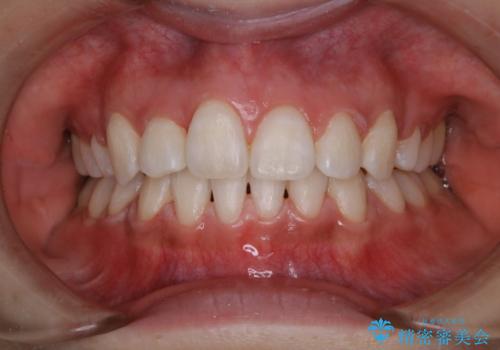

ホワイトニング 1日で真っ白な歯に

- ホワイトニングで歯を白くしたいとのことでした。

処置前クリーニング¥3300・オフィスホワイトニングのエクセレントコース¥29700を行いました。

- ¥33000費用は治療当時の料金となります